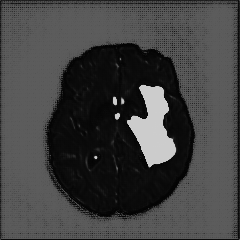

We introduce a neural network framework, utilizing adversarial learning to partition an image into two cuts, with one cut falling into a reference distribution provided by the user. This concept tackles the task of unsupervised anomaly segmentation, which has attracted increasing attention in recent years due to their broad applications in tasks with unlabelled data. This Adversarial-based Selective Cutting network (ASC-Net) bridges the two domains of cluster-based deep learning methods and adversarial-based anomaly/novelty detection algorithms. We evaluate this unsupervised learning model on BraTS brain tumor segmentation, LiTS liver lesion segmentation, and MS-SEG2015 segmentation tasks. Compared to existing methods like the AnoGAN family, our model demonstrates tremendous performance gains in unsupervised anomaly segmentation tasks. Although there is still room to further improve performance compared to supervised learning algorithms, the promising experimental results shed light on building an unsupervised learning algorithm using user-defined knowledge.